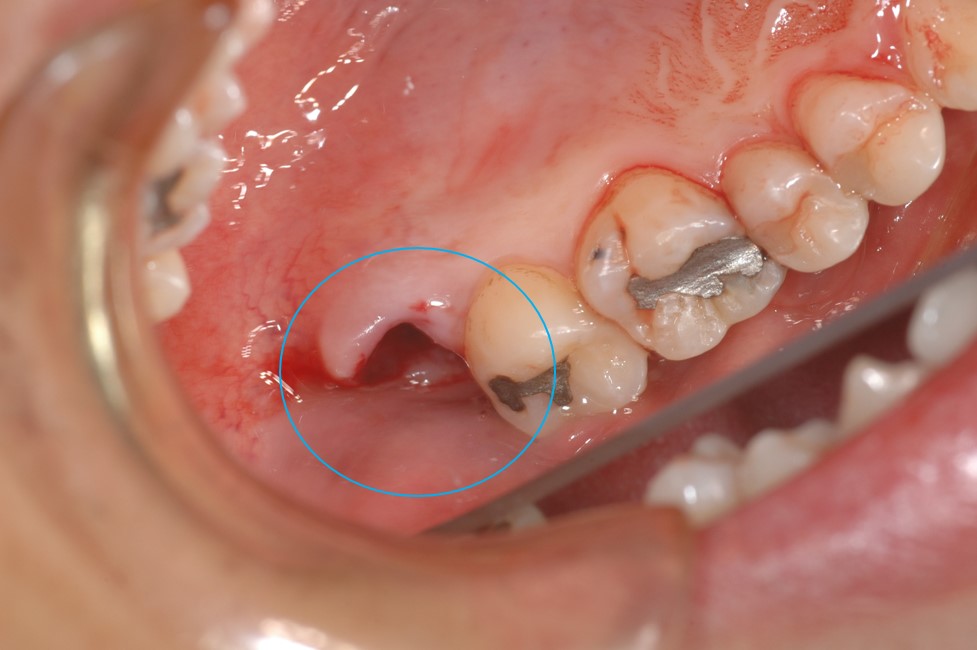

← 174.歯の移植手術(親知らず)